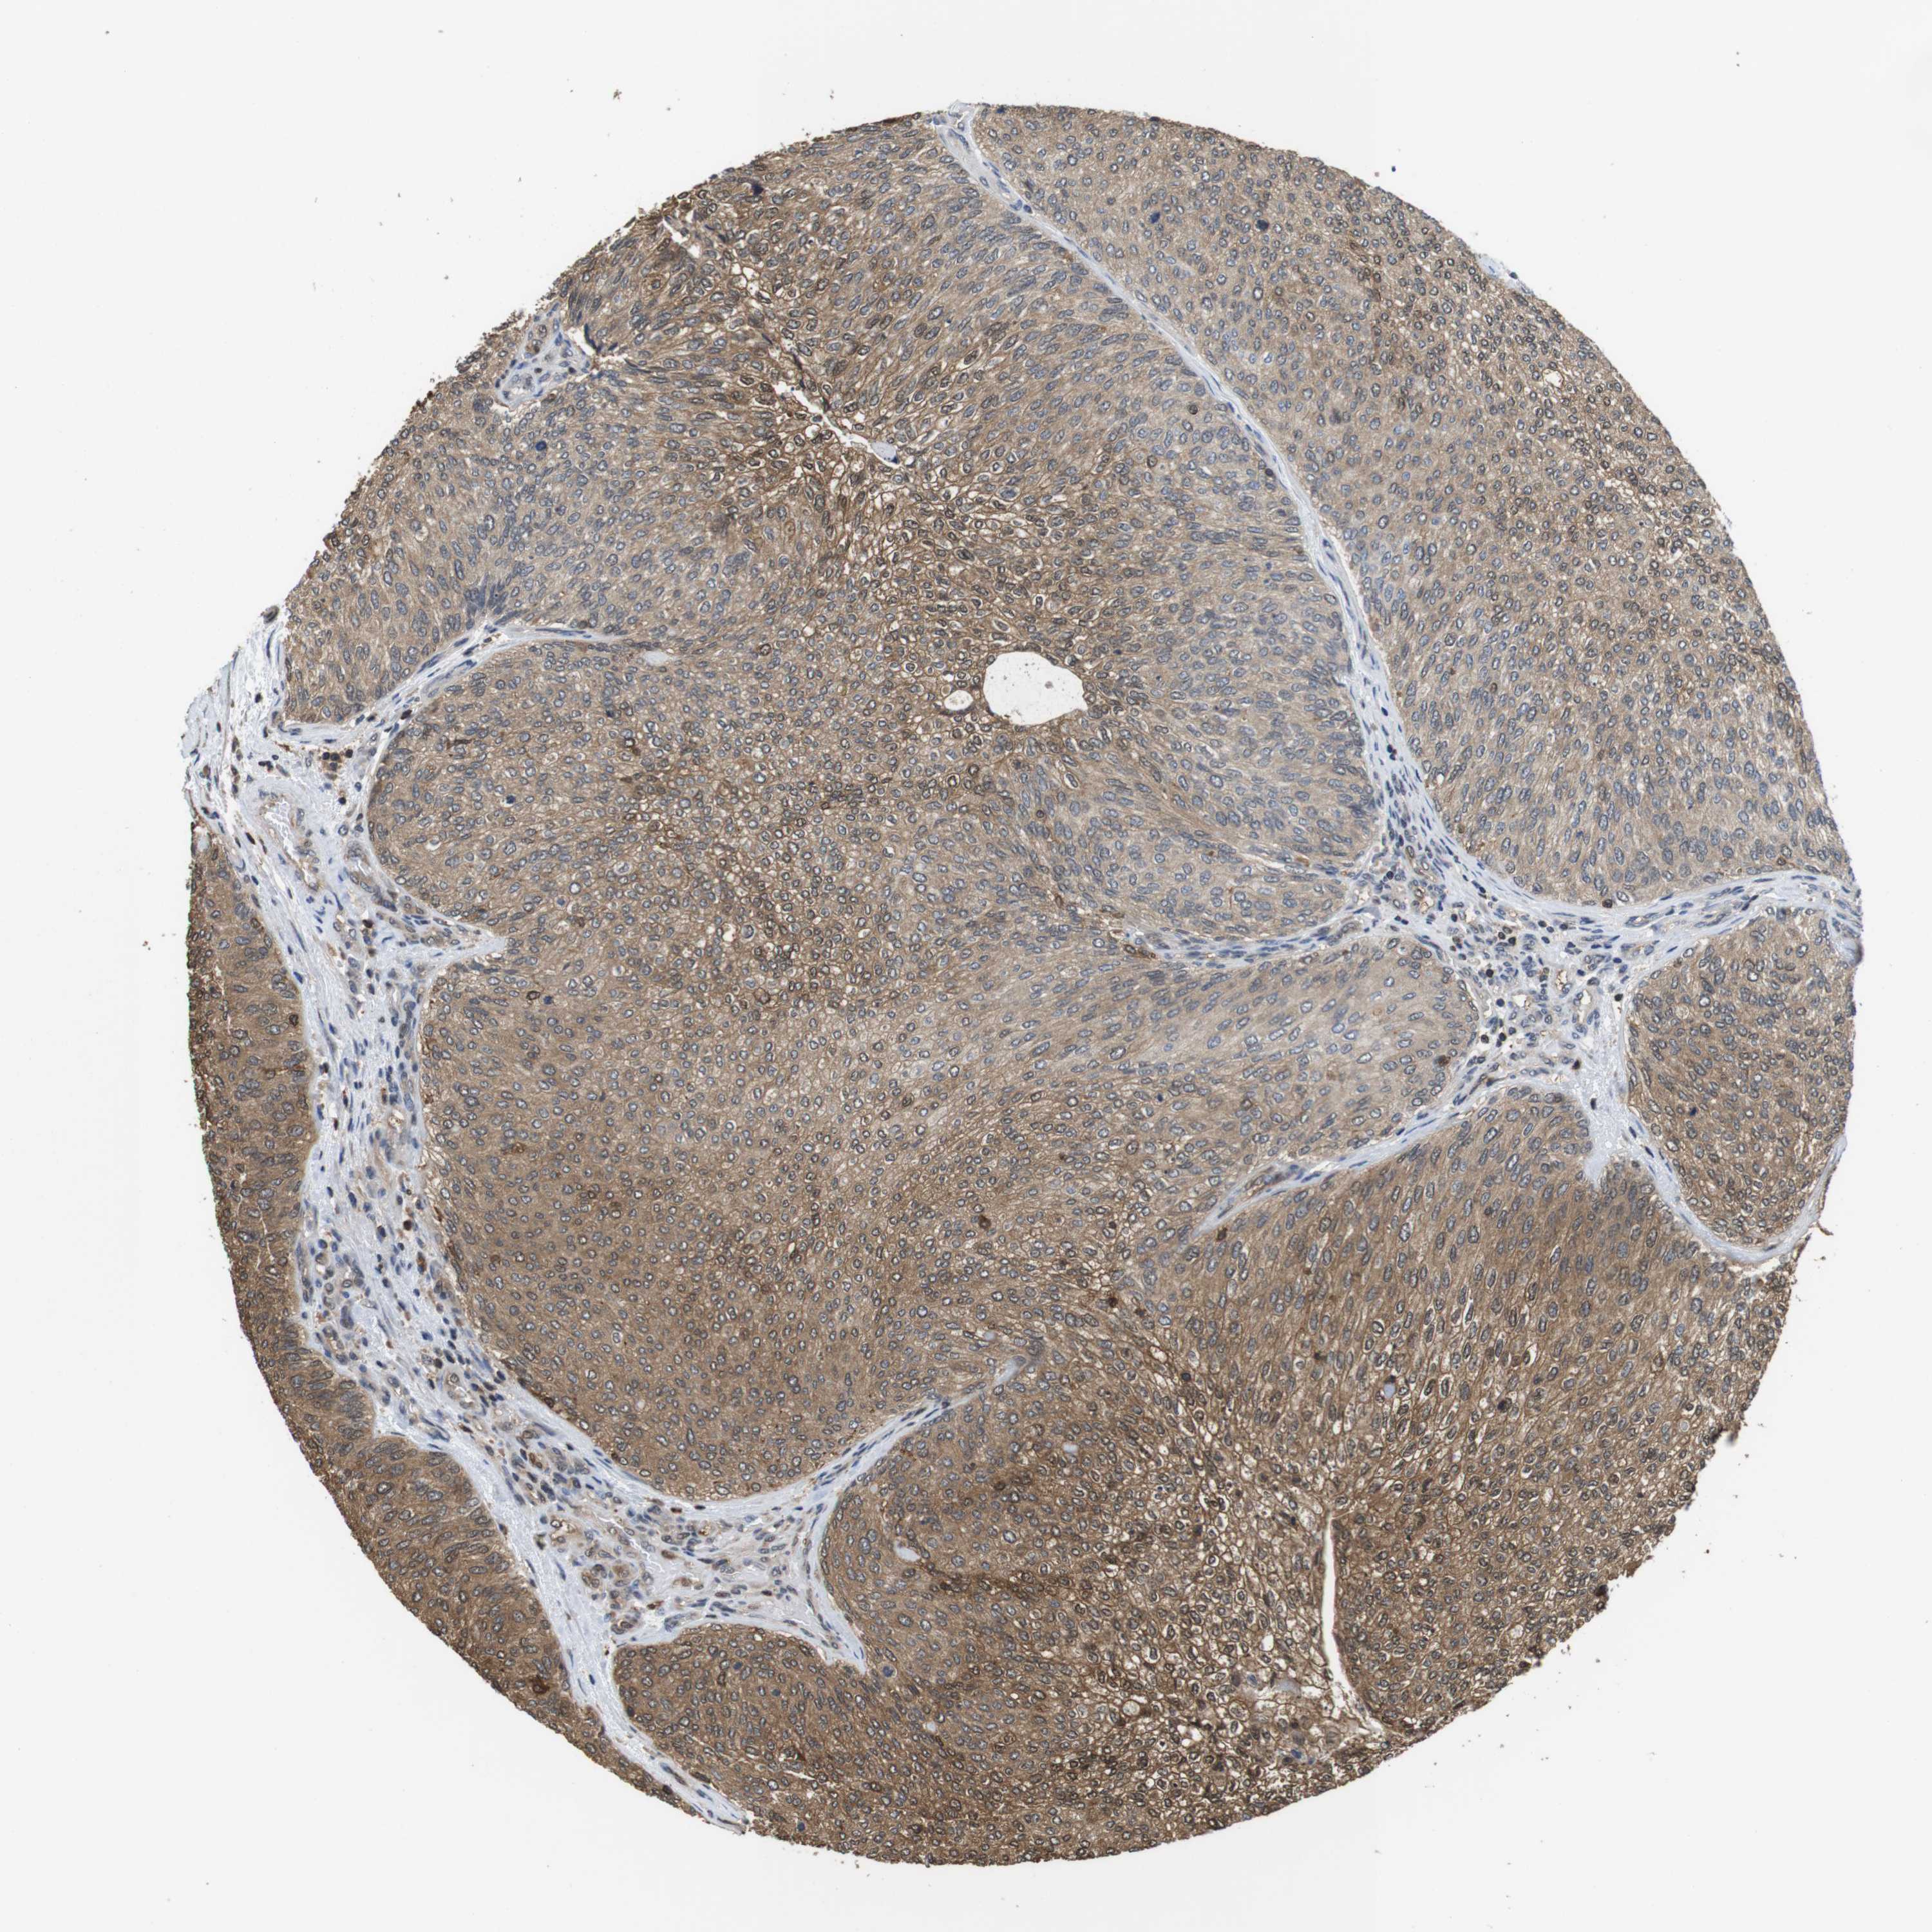

UROTHELIAL CANCER - Protein expressioni

A mouse-over function shows sample information and annotation data. Click on an image to view it in a full screen mode. Samples can be filtered based on level of antibody staining by selecting one or several of the following categories: high, medium, low and not detected. The assay and annotation is described here.

Note that samples used for immunohistochemistry by the Human Protein Atlas do not correspond to samples in the TCGA dataset.

Antibody stainingi

Antibody staining in the annotated cell types in the current human tissue is reported as not detected, low, medium, or high, based on conventional immunohistochemistry profiling in selected tissues. This score is based on the combination of the staining intensity and fraction of stained cells.

Each image is clickable and will lead to virtual microscopy that enables deeper exploration of all samples and also displays staining intensity scores, fraction scores and subcellular localization as well as patient and tissue information for each sample.

Antibody CAB015336

Antibody CAB069404

Staining

High

Medium

Low

Not detected

Intensity

Strong

Moderate

Weak

Negative

Quantity

>75%

75%-25%

<25%

None

Location

Nuclear

Cytoplasmic/membranous

Cytoplasmic/membranous,nuclear

Urothelial carcinoma, Low grade

Urothelial carcinoma, High grade

Urothelial carcinoma, NOS